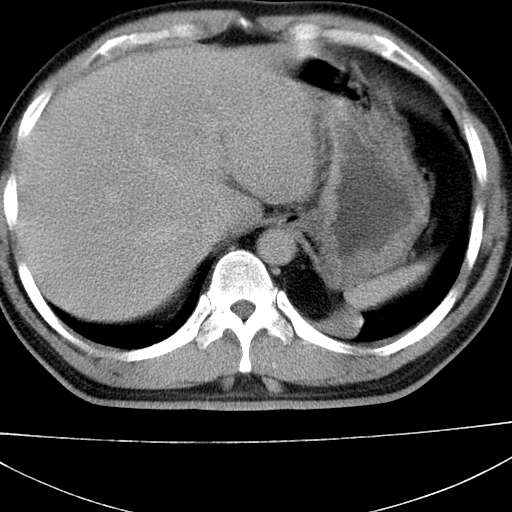

标题: CT21921:腹膜后腔肿物。患者男39Y。体检。增强扫描时间欠准 [打印本页]

标题: CT21921:腹膜后腔肿物。患者男39Y。体检。增强扫描时间欠准

1)考虑左肺下叶后基底段(或左下胸后壁胸膜)软组织团块,性质待定;建议行进一步检查。2)左肾结石。

左膈肌连续性中断,左侧膈疝可能性大.

左膈肌角后腹膜腔见肿物影,其内见脂肪密度灶及软组织密度灶,强化不明显。病灶大部在后腹膜内。考虑异位嗜铬细胞瘤或脂肪肉瘤、畸胎瘤